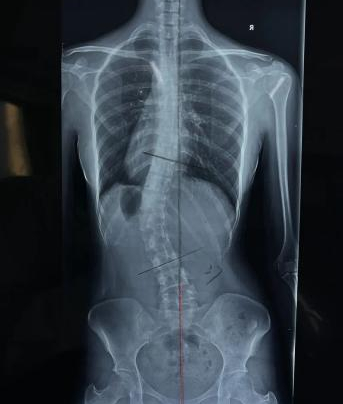

脊柱侧凸检查影像